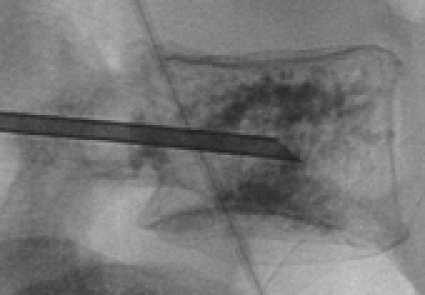

Båda teknikerna kan utföras i lokalanestesi, och i USA utförs ingreppet ofta som dagkirurgi, vilket är ovanligt i Europa. Vid båda teknikerna placeras patienten i bukläge, där man genom yttre stöd försöker minska kyfosen i det skadade området. Härefter anlägger man en perkutan ingång från ryggsidan där man för in en ledare med en troakar genom kotans pedikel (bågbas), eller i bröstryggen lateralt om pedikeln, in i den frakturerade kotkroppen (Figur 4),

Vid vertebroplastik infiltreras därefter den skadade kotan med visköst bencement under röntgenologisk genomlysning (Figur 2). Vid cementeringen måste man vara försiktig så att cement inte läcker in i spinalkanalen, där ryggmärgen eller nervrötter kan komprimeras.